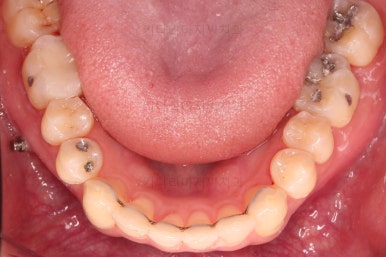

초진 시 입안의 모습입니다.

앞니가 약간 삐뚠 것 말고는 큰 문제는 없어보이네요.

장치를 부착했습니다.

이번 부산연제구교정 환자분이 선택한 장치는 엠파워 클리어라고 하는 자가결찰 세라믹 장치입니다.

최대한 빠른 시일 내에 치열을 가지런하게 해주고 미니스크류를 많이 식립하게 됩니다.